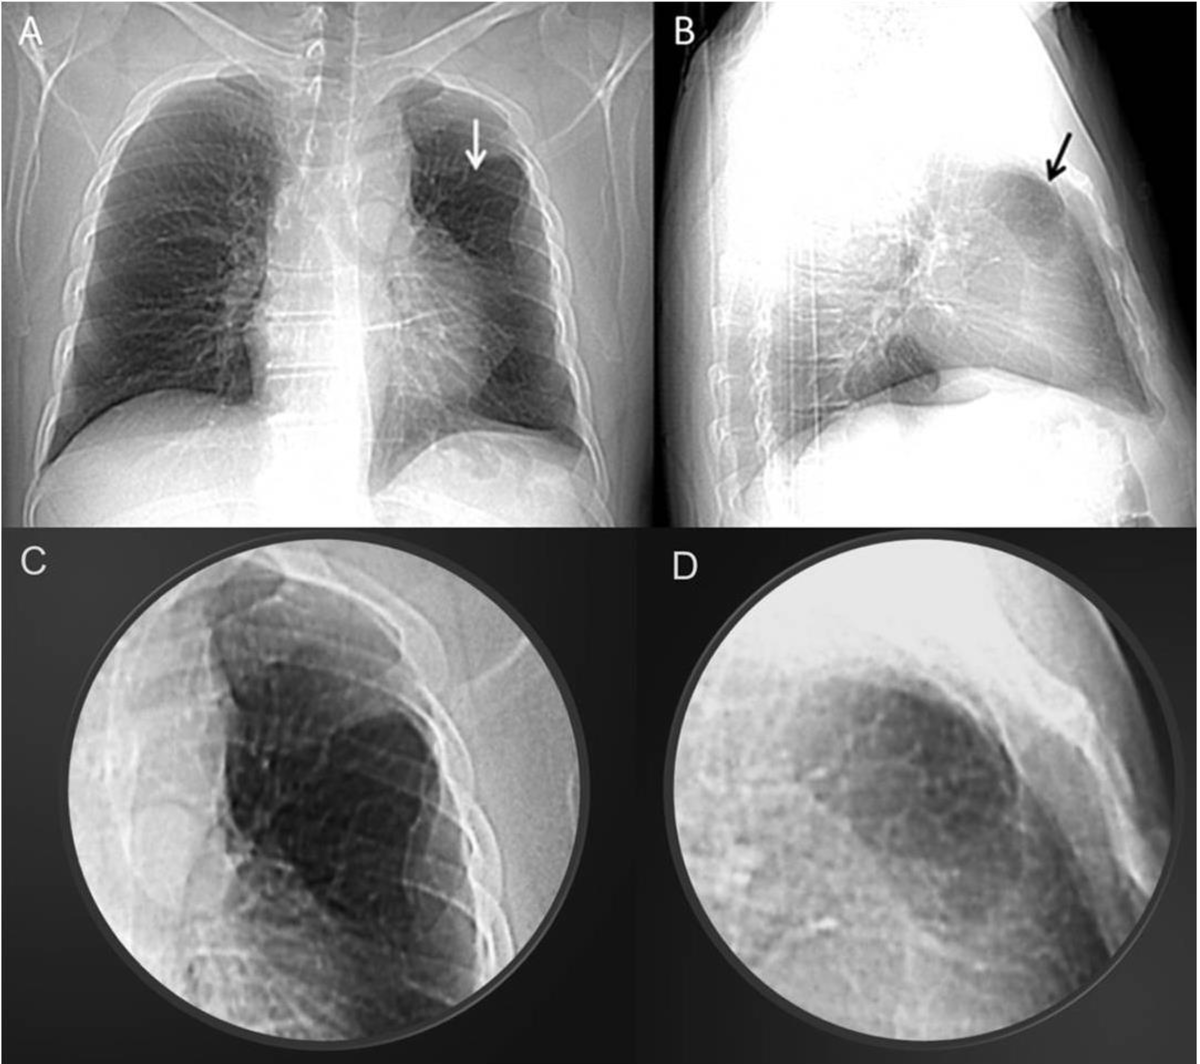

40歳男性の肺ヘルニア

A)左上葉の透過性亢進(白矢印)

B)境界明瞭な卵円形の透過性亢進域(黒矢印)

C,D)A,Bの拡大像